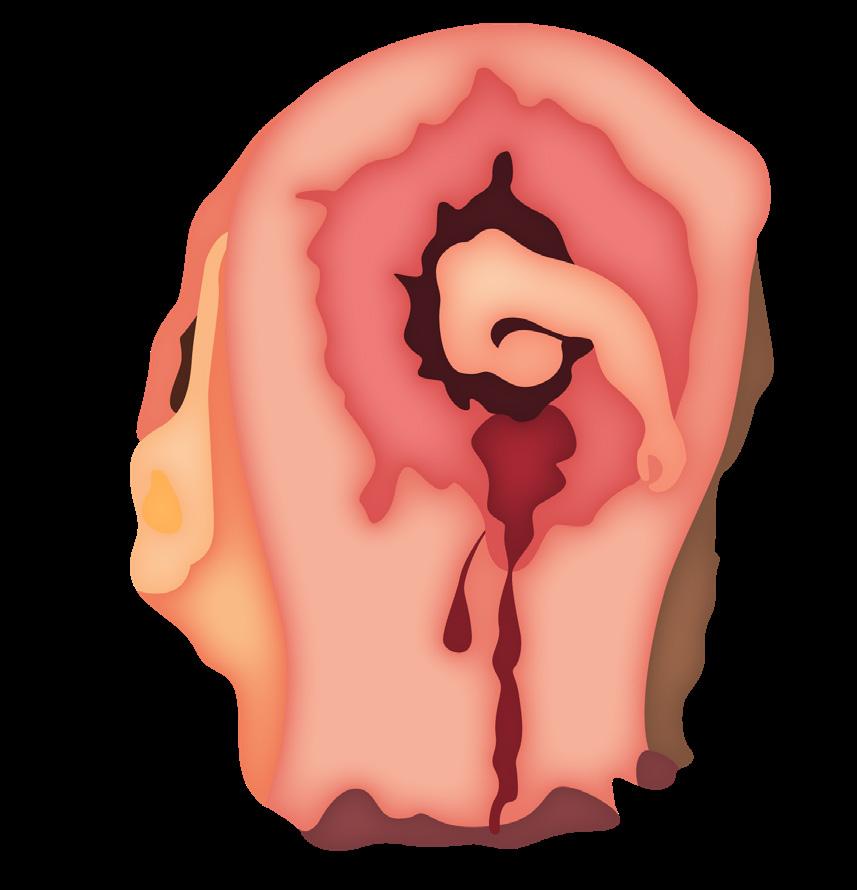

Hemorragia fetal (ENARM 2007) por la localización de los vasos fetales cerca al orificio cervical interno.

La clínica es un sangrado súbito posterior a la rotura artificial de membrana (amniotomía) durante el trabajo de parto, seguida de una hipoxia fetal (bradicardia fetal o patrón sinusoidal) (ENARM 2019). Se confirma con una ecografía Doppler.